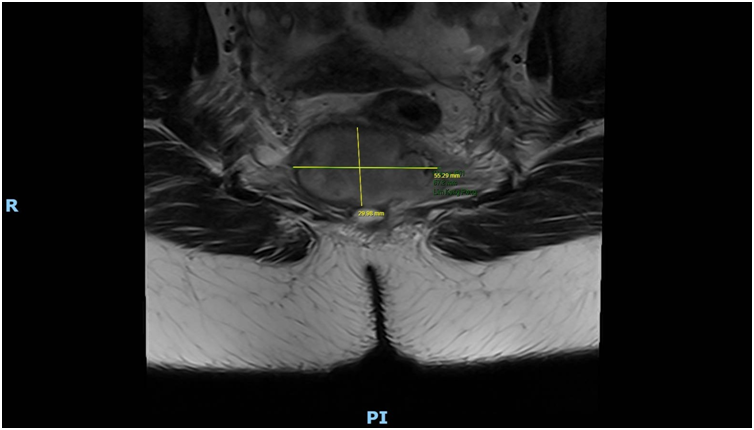

Imaging via MRI and CT demonstrated a complex, encapsulated lesion with peripheral enhancement and restricted diffusion. Multidisciplinary evaluation suggested a congenital epidermoid or duplication cyst. Given the absence of malignancy and surgical complexity, a conservative management strategy was adopted.

Figure 1: Figure 1 Duplication cyst 2025 MRI sagittal plane

Figure 2: Figure 2 Duplication cyst 2025 MRI sagittal plane

Figure 3: Figure 3 Duplication cyst 2020 Coronal plane

Figure 4: Figure 4 Duplication cyst 2020 sagittal plane

Figure 5: Figure 5 Duplication cyst axial 2020 plane post cystic aspiration

Figure 6: Figure 6 Duplication cyst 2025 sagittal plane

Figure 7: Figure 7 Duplication cyst 2025 MRI axial plane

Figure 8: Figure 8 Duplication cyst 2020 axial plane